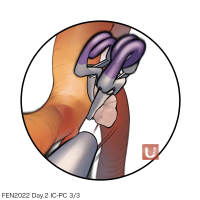

FEN2022シリーズ